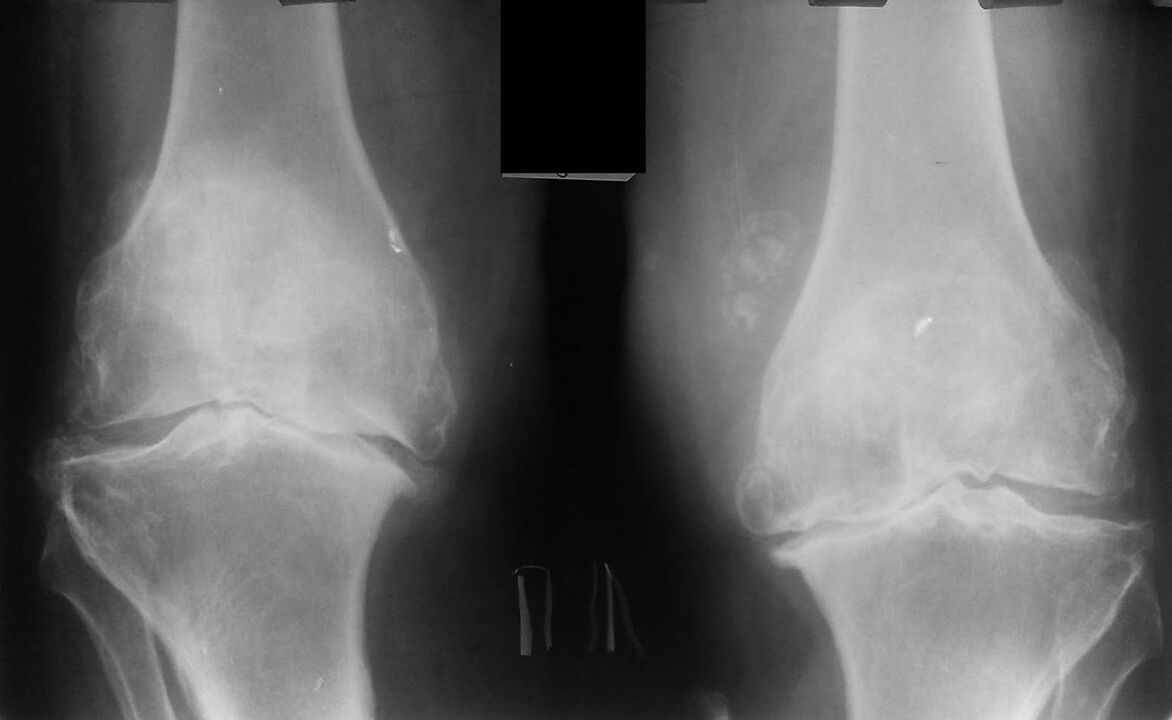

Este diagnóstico se realiza sobre la base de las quejas del paciente, los datos del examen, la palpación de la articulación enferma y el examen de rayos X.

La radiografía es un método de investigación estándar que le permite confirmar el diagnóstico, establecer el grado de cambios patológicos, monitorear la dinámica del proceso y también le permite excluir otros procesos patológicos (por ejemplo, tumores) en la tibia y el fémur. .

Cabe señalar que los cambios primarios en las estructuras de la articulación de la rodilla en las radiografías pueden estar ausentes. Posteriormente se determina el estrechamiento del espacio articular y la compactación de la zona subcondral. Los extremos articulares del fémur y especialmente de la tibia se expanden, los bordes de los cóndilos se vuelven puntiagudos.

Los métodos de diagnóstico auxiliares son la TC (tomografía computarizada) y la RM (resonancia magnética), que permiten un estudio más detallado de los cambios patológicos en las estructuras óseas e identifican cambios en los tejidos blandos.